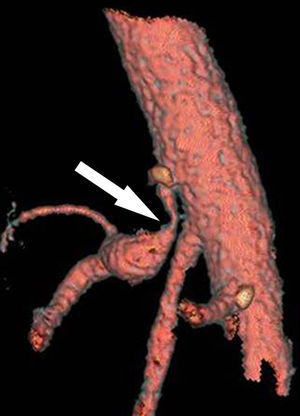

Reconstrucción vascular (TCMD) en inspiración forzada del mismo paciente. Se visualiza el segmento proximal del tronco celíaco con la típica morfología en forma de “gancho” y estenosis de su luz en el origen por impronta de ligamento arcuato mediano (flecha), y dilatación posestenótica: síndrome del ligamento arcuato mediano. (Tomado de Soliva Martínez D, Fernández Iglesias P, Belda González I, Martínez Yunta JA, Hernández Muñoz L, Blanco López ME. Hallazgos poco conocidos en el síndrome del ligamento arcuato mediano. 10.1594/seram2014/S-0407).